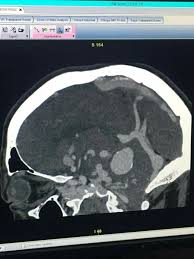

Cerebrospinal Fluid Pseudo Cyst As A Complication Of Ventriculoperitoneal Shunt Other Complications May Include Abdominal Cerebrospinal Fluid Cysts Pancreas

Mesentric Peritoneal Inclusion Cyst Radiology Cysts Cavities